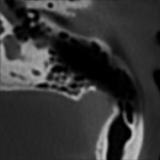

In the proposed method, preoperative CT ρ𝜌\rhoitalic_ρ and postoperative CT Ο‰πœ”\omegaitalic_Ο‰ are aligned via rigid registration, and their intensity values are normalized in the preprocessing step. As shown in Fig. 1, the removed mastoid volume during surgery tends to have a low-intensity distribution in Ο‰πœ”\omegaitalic_Ο‰. Thus, we develop a model to predict the mastoidectomy region, represented as δ𝛿\deltaitalic_Ξ΄, on ρ𝜌\rhoitalic_ρ and make the predicted preoperative CTs (ΟβŠ—Ξ΄tensor-productπœŒπ›Ώ\rho\otimes\deltaitalic_ρ βŠ— italic_Ξ΄) have higher similarity when compared with Ο‰πœ”\omegaitalic_Ο‰. The neural network shown in Fig. 2 is modeled as a function fΞΈsubscriptπ‘“πœƒf_{\theta}italic_f start_POSTSUBSCRIPT italic_ΞΈ end_POSTSUBSCRIPT(ρ𝜌\rhoitalic_ρ) = δ𝛿\deltaitalic_Ξ΄ using the state-of-the-art SegMamba-based [8] neural network with a pretrained SAM-Med3D [9] encoder as our feature extractor, where ΞΈπœƒ\thetaitalic_ΞΈ is the set of neural network parameters. In our model, we reduce the original CT dimensions to [160,160,64]16016064[160,160,64][ 160 , 160 , 64 ] by cropping around the ear regions using an ear anatomy segmentation neural network proposed in [10].

Figure 1: Framework overview. We compare the predicted mastoidectomy-removed region applied to the preoperative CT ΟβŠ—Ξ΄tensor-productπœŒπ›Ώ\rho\otimes\deltaitalic_ρ βŠ— italic_Ξ΄ against the postoperative CT Ο‰πœ”\omegaitalic_Ο‰ using similarity-based loss function Lm⁒s⁒s⁒s⁒i⁒m⁒_⁒c⁒s⁒c⁒csubscriptπΏπ‘šπ‘ π‘ π‘ π‘–π‘š_𝑐𝑠𝑐𝑐L_{msssim\_cscc}italic_L start_POSTSUBSCRIPT italic_m italic_s italic_s italic_s italic_i italic_m _ italic_c italic_s italic_c italic_c end_POSTSUBSCRIPT. A smoothing term Ls⁒m⁒o⁒o⁒t⁒hsubscriptπΏπ‘ π‘šπ‘œπ‘œπ‘‘β„ŽL_{smooth}italic_L start_POSTSUBSCRIPT italic_s italic_m italic_o italic_o italic_t italic_h end_POSTSUBSCRIPT is also applied to δ𝛿\deltaitalic_Ξ΄ to further reduce noise output by network fΞΈsubscriptπ‘“πœƒf_{\theta}italic_f start_POSTSUBSCRIPT italic_ΞΈ end_POSTSUBSCRIPT.